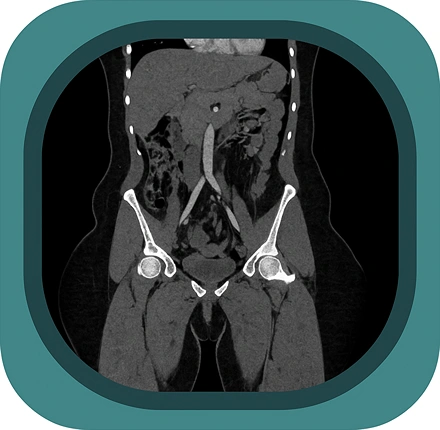

Explore full-body CT anatomy in 3 planes. Our high-resolution, carefully labelled images reveal micro-anatomy—ideal for radiologists, radiographers and surgeons.